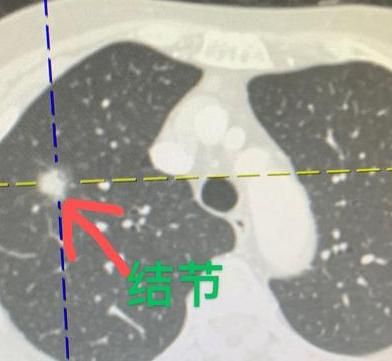

“医生,我的肺结节是不是转移了?”一大早刚开诊,一位患者就急匆匆地找到我。她今年57岁,半年前刚做了肺磨玻璃结节手术,病理结果是微浸润癌。 虽然手术很成功,但她心里一直不踏实,最近自己去做了个颈部B超,发现淋巴结有点肿大,一下子就慌了神,担心是不是转移复发。 其实,从肺癌术后的规范复查来看,颈部B超并不属于常规推荐的检查项目。我们每个人的颈部都有淋巴结,平时感冒、喉咙发炎、扁桃体发炎等,都可能导致淋巴结肿大。 甚至以前有过炎症,也可能留下一些良性增生,所以不一定就和肿瘤有关。 如果大家也遇到类似情况,先别过度紧张。绝大多数颈部淋巴结肿大都是炎症引起的,跟肺癌转移没有直接关系。 特别是像她这种肺磨玻璃结节的微浸润癌,做完手术之后复发转移的概率本身就很低。当然,如果淋巴结肿大很明显,比如到了2、3公分,或者持续不消退,那也可以考虑做穿刺活检明确一下性质,这样自己也更安心。[玫瑰][谢谢]